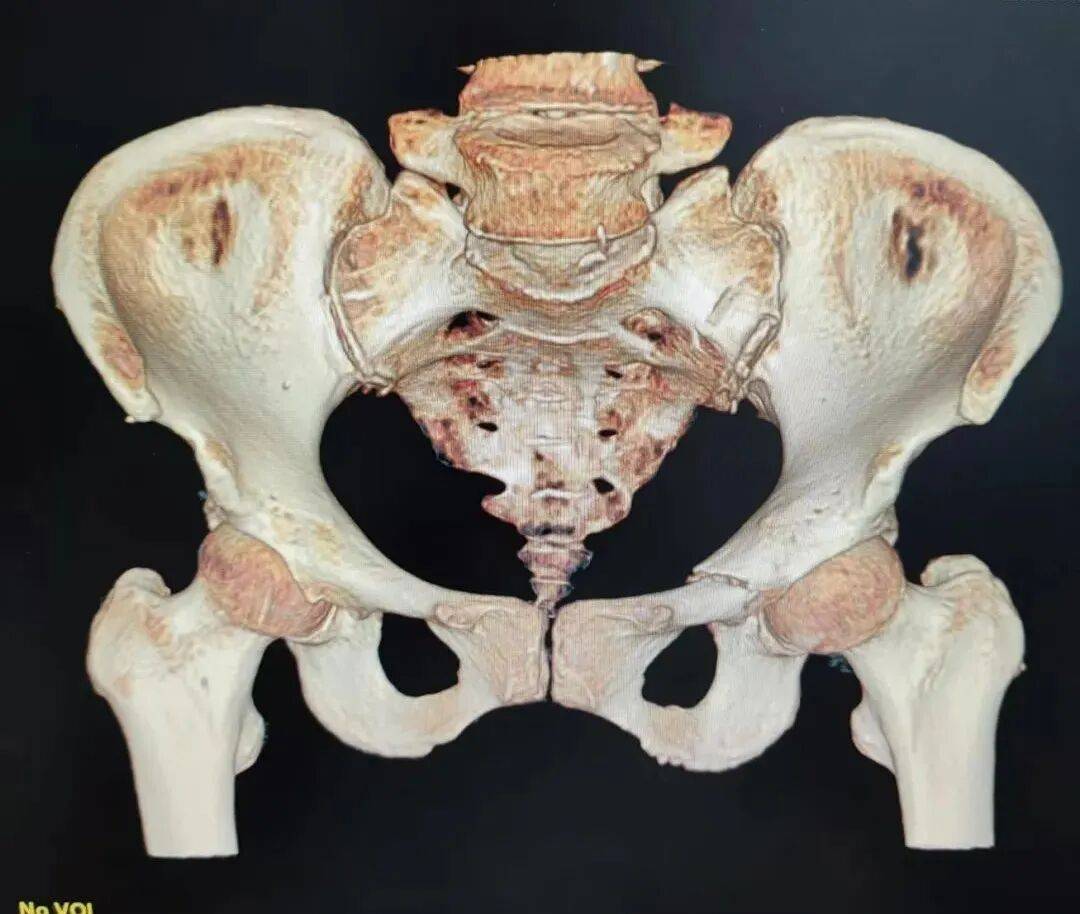

入院后,急诊科的医生们为姬奶奶安排了全面细致的检查。经过一番仔细的诊断,姬奶奶不仅骨盆骨折和左桡骨远端骨折,还合并了低钠血症、双侧肺炎伴胸腔积液、低蛋白血症以及左侧腘静脉血流瘀滞等多种基础疾病,病情复杂程度超乎想象。

经过充分的术前准备,急诊科团队决定为姬奶奶实施骨盆骨折通道螺钉内固定术。与传统手术相比,它具有创伤小、恢复快、并发症少等诸多优势。手术室内,气氛紧张而严肃。医生们全神贯注,凭借着精湛的技术和丰富的经验,精准地将螺钉植入姬奶奶的骨盆骨折部位,固定骨折断端。每一个动作都小心翼翼,每一个步骤都精准无误,整个手术过程如行云流水般顺畅。